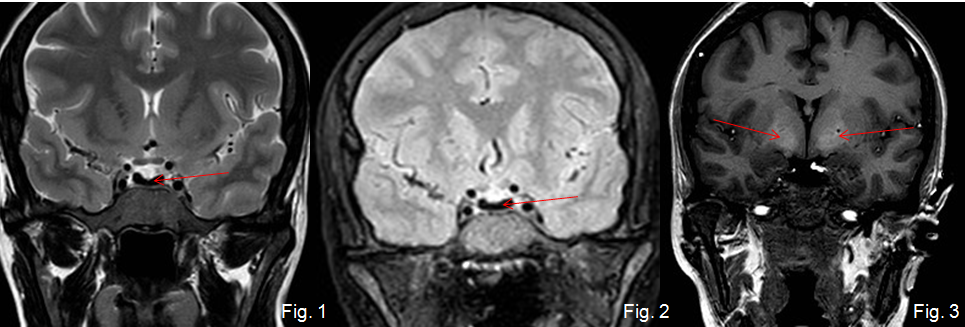

Mujer de 37 años con amenorrea que ingresa por poliuria y polidipsia. Antecedentes de anemia hemolítica no inmune, esplenectomizada. En tratamiento con metformina.

Depósito de hierro en la hipófisis secundario a hemocromatosis secundaria produciendo un hipogonadismo hipogonadotrófico.

La hemocromatosis secundaria es una enfermedad caracterizada por el depósito de hierro en el hígado y en otros órganos. El hierro se puede depositar en la hipófisis, ocasionando un hipogonadismo hipogonadotrofo.

En esta paciente se observa, además del depósito de hierro en la hipófisis, una hiperintensidad de señal de los ganglios basales, hallazgos que pueden ver en la degeneración hepatocerebral adquirida.

Tras la realización de esta RM hipofisaria se le realizaron a la paciente RM de abdomen y de corazón, existiendo también depósito de hierro hepático, pancreático y miocárdico, con diabetes mellitus secundaria.